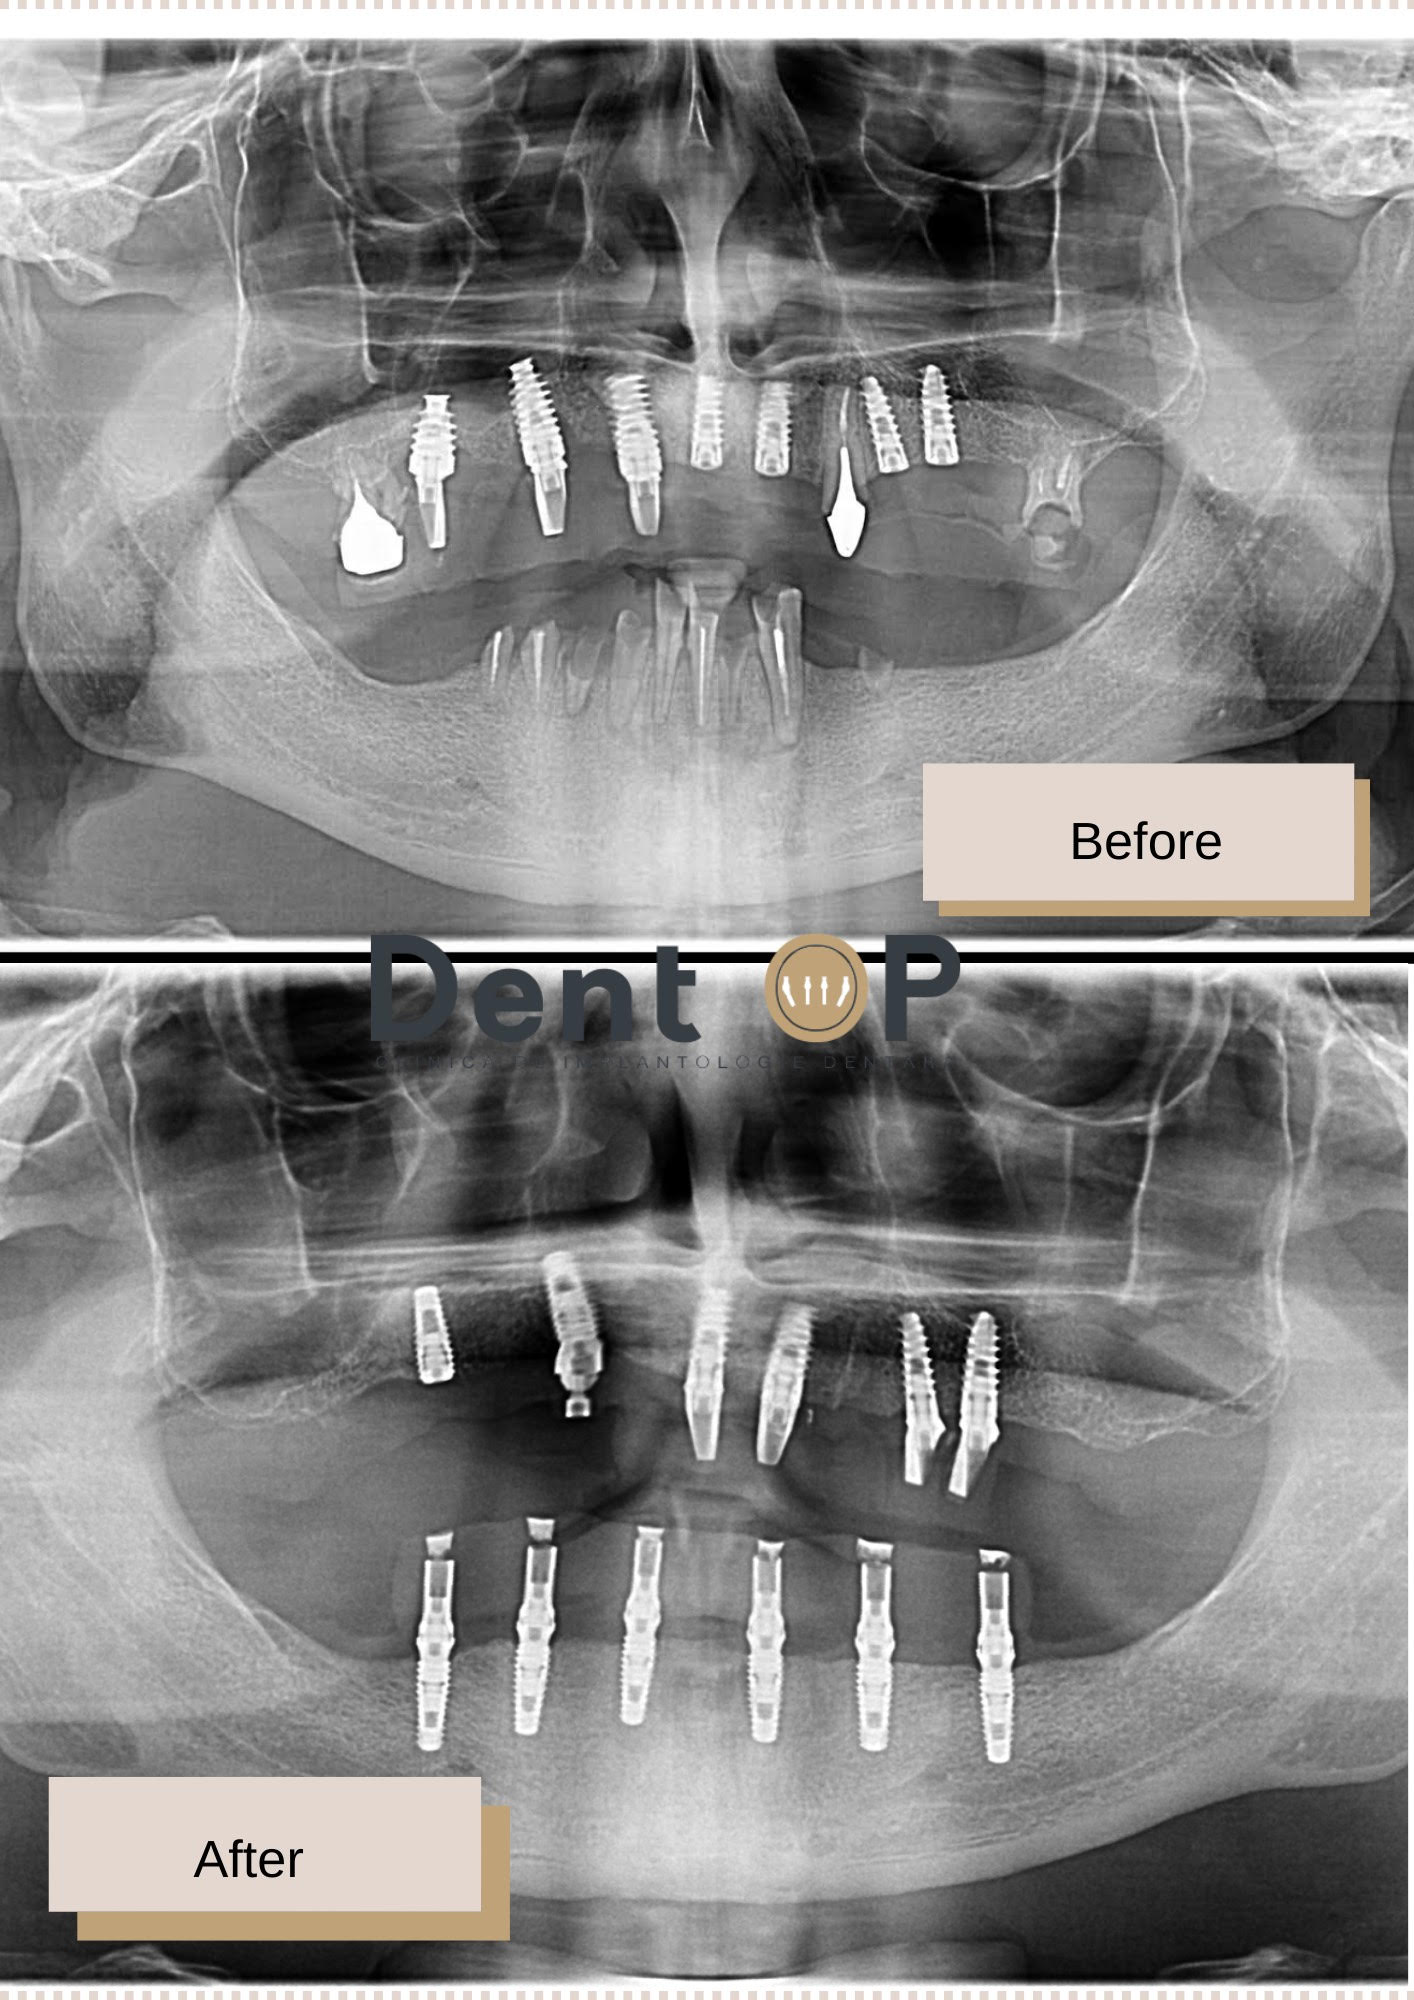

Domnul E. s-a prezentat cu o serie de implanturi vechi la maxilar, care nu-l mai ajutau să se hrănească corespunzător. În partea de jos, la mandibulă, pacientul mai avea doar câteva rădăcini.

În cadrul unei consultații alături de Dr Cazacu Corrado – Medic Specialist Chirurgie Dento-Alveolară, s-a constatat nevoia extragerii implanturilor vechi și a rădăcinilor rămase și inserarea a 12 implanturi dentare. Intervenția a fost posibilă datorită Sedării Conștiente, procedură cu ajutorul căreia pacientul nu a simtit absolut nimic pe tot parcursul intervenției.